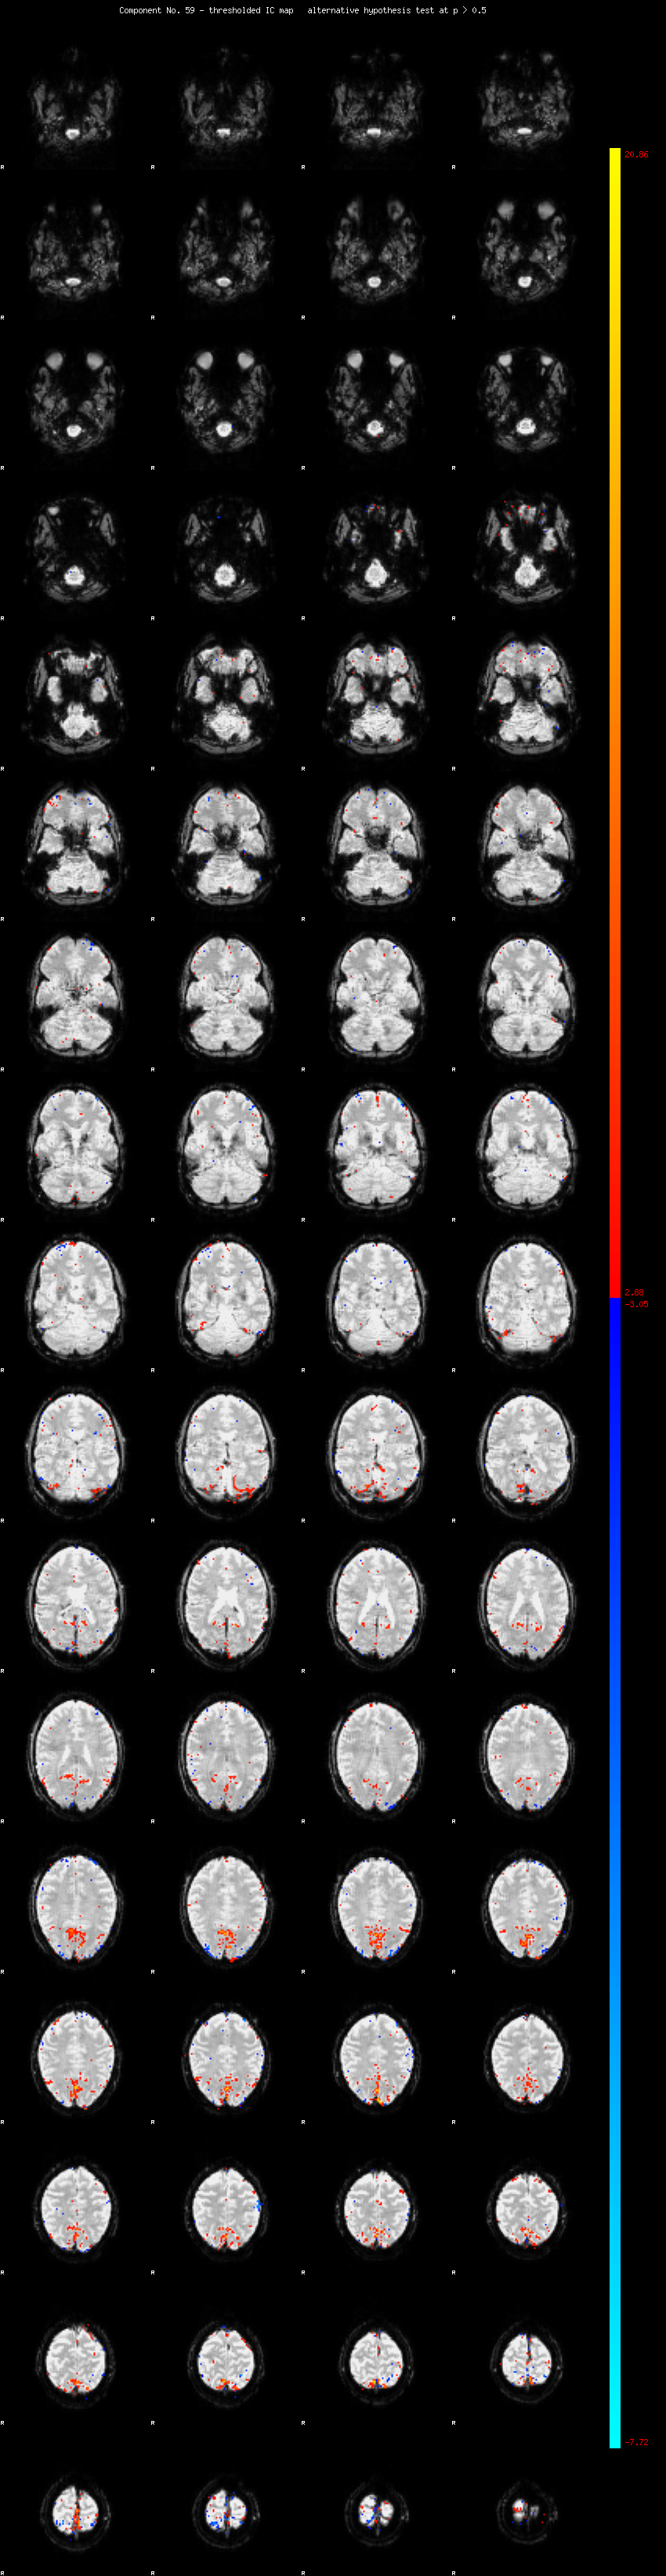

MELODIC Component 59

0.86 % of explained variance;     0.57 % of total variance

MMfit